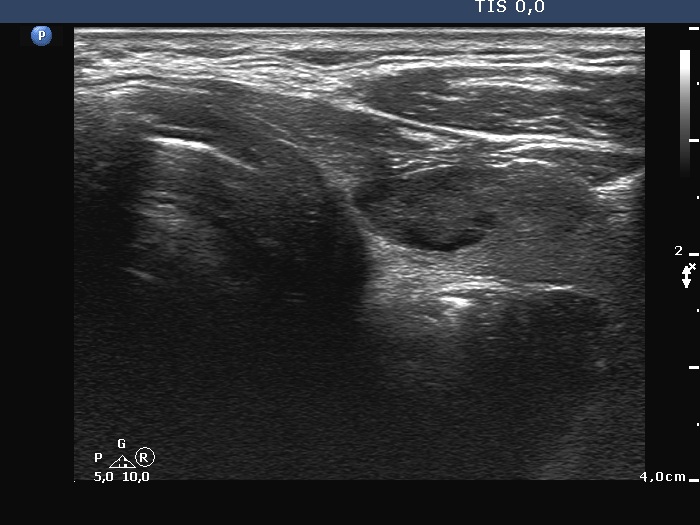

Ultrasonography. The right lobe was extremely enlarged with the dimensions of 50, 50 and 85 mm, depth, width and length, respectively. This lobe was composed of multiple hypoechoic areas within an echonormal background. The left lobe also had a hypoechoic lesion.